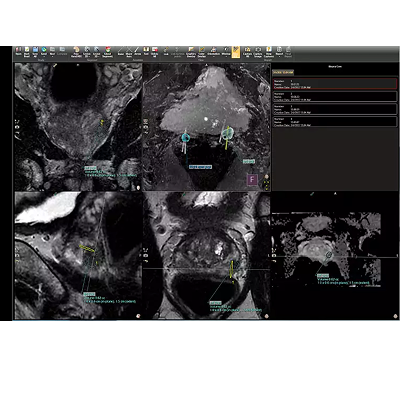

凭借功能强大、易于导航的多供应商 MR 图像分析系统,DynaCAD 可以快速处理和管理大量数据。您可以以即读的自定义悬挂协议打开箱子,所有图像都同步,以便轻松进行多参数审查。

可调节的 3D 分割,用于最佳引导的活检

您可以减少前列腺的手动轮廓:DynaCAD Prostate 基于模型的腺体分割会自动执行腺体的 3D 分割。您可以更改或调整所有三个平面中的分割结果。由此产生的分割报告了总体腺体体积,并为 UroNav MR/US 引导的融合活检程序奠定了基础。

用户生成的 ROI 可以显示在前列腺的 3D 模型以及研究中的多个图像序列上。